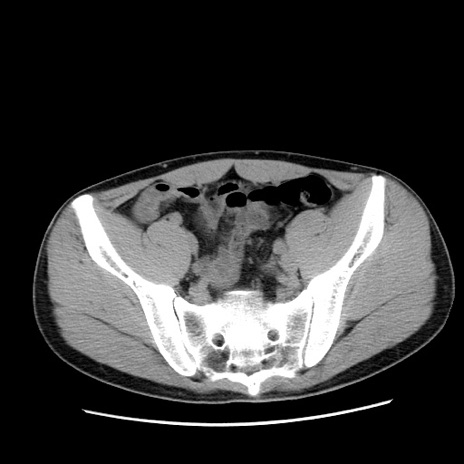

冠状断像

症例36(横断像)

【症例】20歳代 男性

【主訴】心窩部痛

【現病歴】今朝より上腹部痛あり。一旦軽快していたが再度出現したため救急要請。昨日夕に白身の魚を含む刺身を食べた。

【身体所見】BP 136/89mmHg、HR 74/min、BT 37.0℃、腹部:膨満、軟、心窩部に圧痛あり。反跳痛なし、筋性防御なし、腸雑音やや亢進あり。

【データ】WBC 17700、CRP 0.48